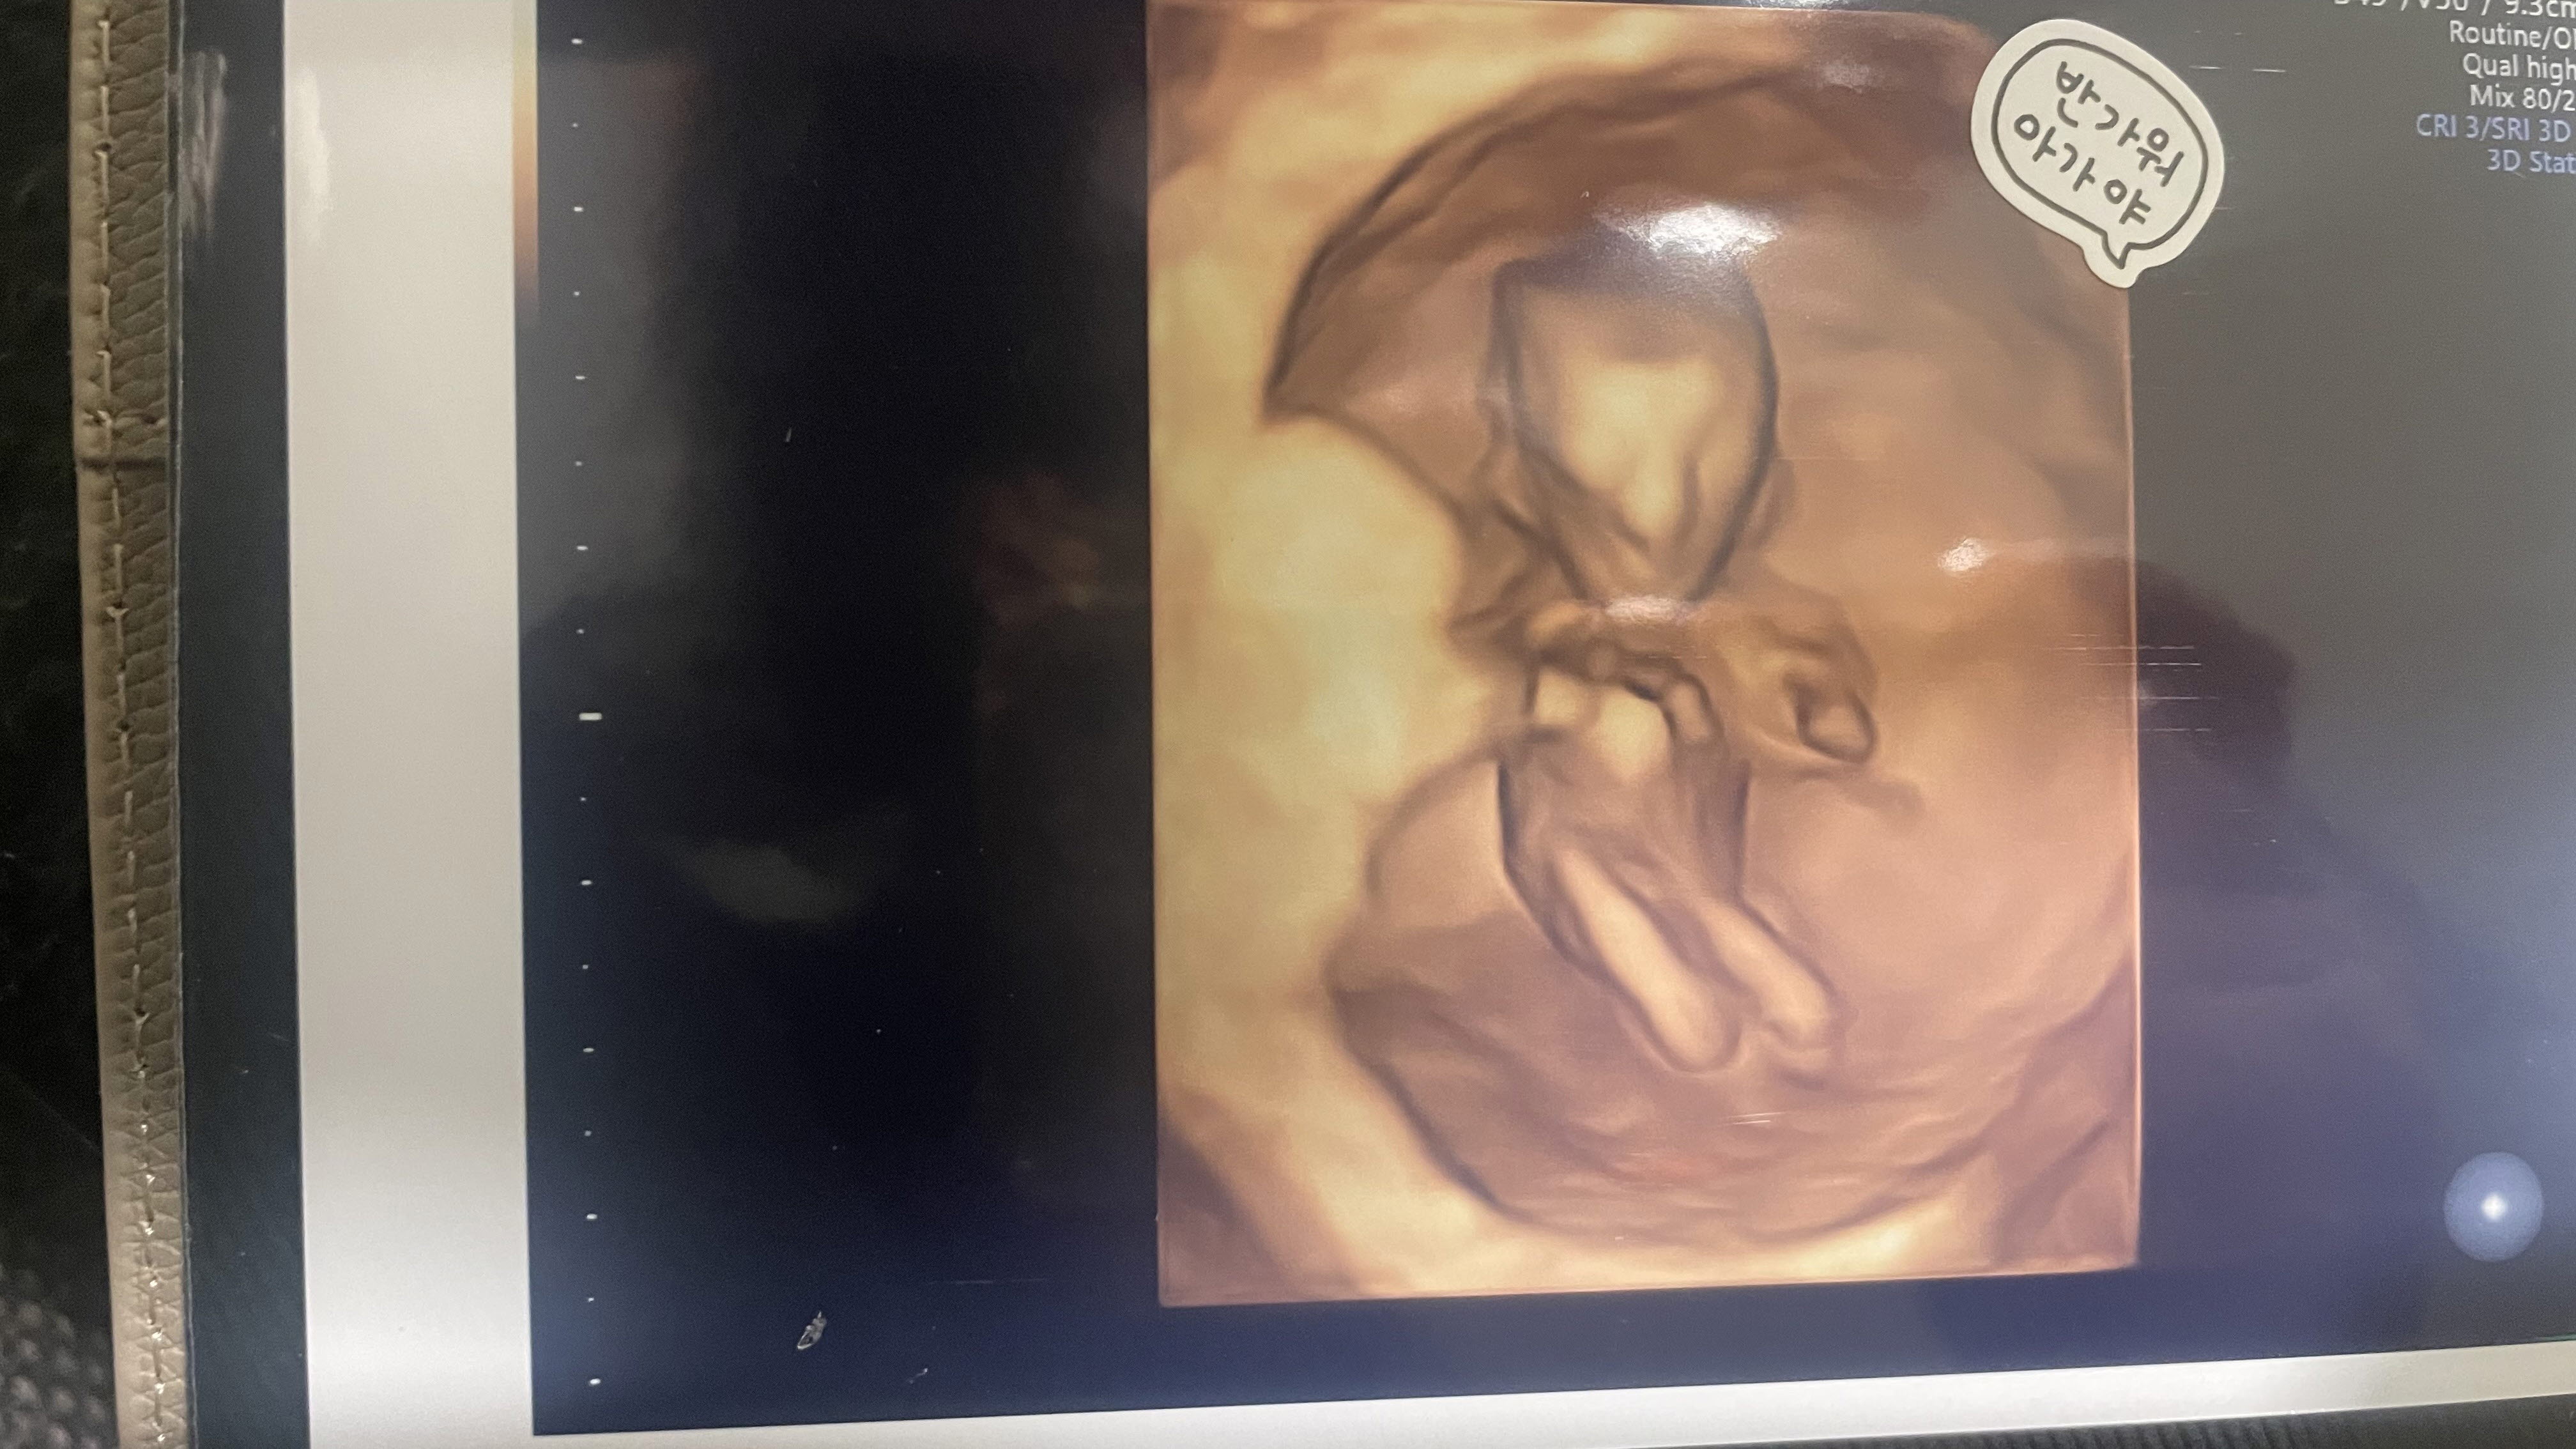

그리고 2023년 6월 15일에 알게된 우리 태공의 존재.

벌써 5개월에 접어들었고,

태공이를 만나기 까지 딱 절반의 시간이 지났다.

태공이가 건강하게만 나와주기를..

손가락 열개, 발가락 열개, 눈, 코, 입, 귀, 장기와 세포 모든 기관들이 정상적으로 잘 성장해서 하나님의 창조의 완벽함 그대로 만나게 되기를 기도한다.

태공아..

지금도 뱃속에서 꼬물꼬물... 하고 있는 너를 느끼는게 엄마는 참 신기하고 묘하고 좋아!

네가 잘 지내고 있다고 엄마한테 사인을 보내는 것 같아서!